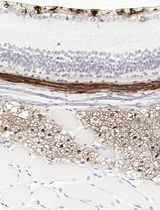

Improved Immunohistochemistry of Mouse Eye Sections Using Davidson's Fixative and Melanin Bleaching

Anne Nathalie Longakit [...] Catherine D. Van Raamsdonk

Nov 20, 2025 1624 Views